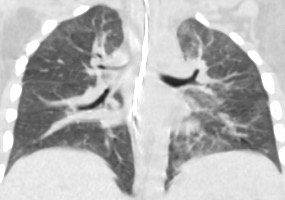

1926. Пациент 2 лет с нейробластомой левого надпочечника после нескольких блоков полихимио- и лучевой терапии и туморадреналэктомии слева, на КТ выявлено снижение пневматизации легочной ткани, диффузно расположенные участки уплотнения легочного интерстиция по типу «лоскутного одеяла», рентгенологическая картина соответствует